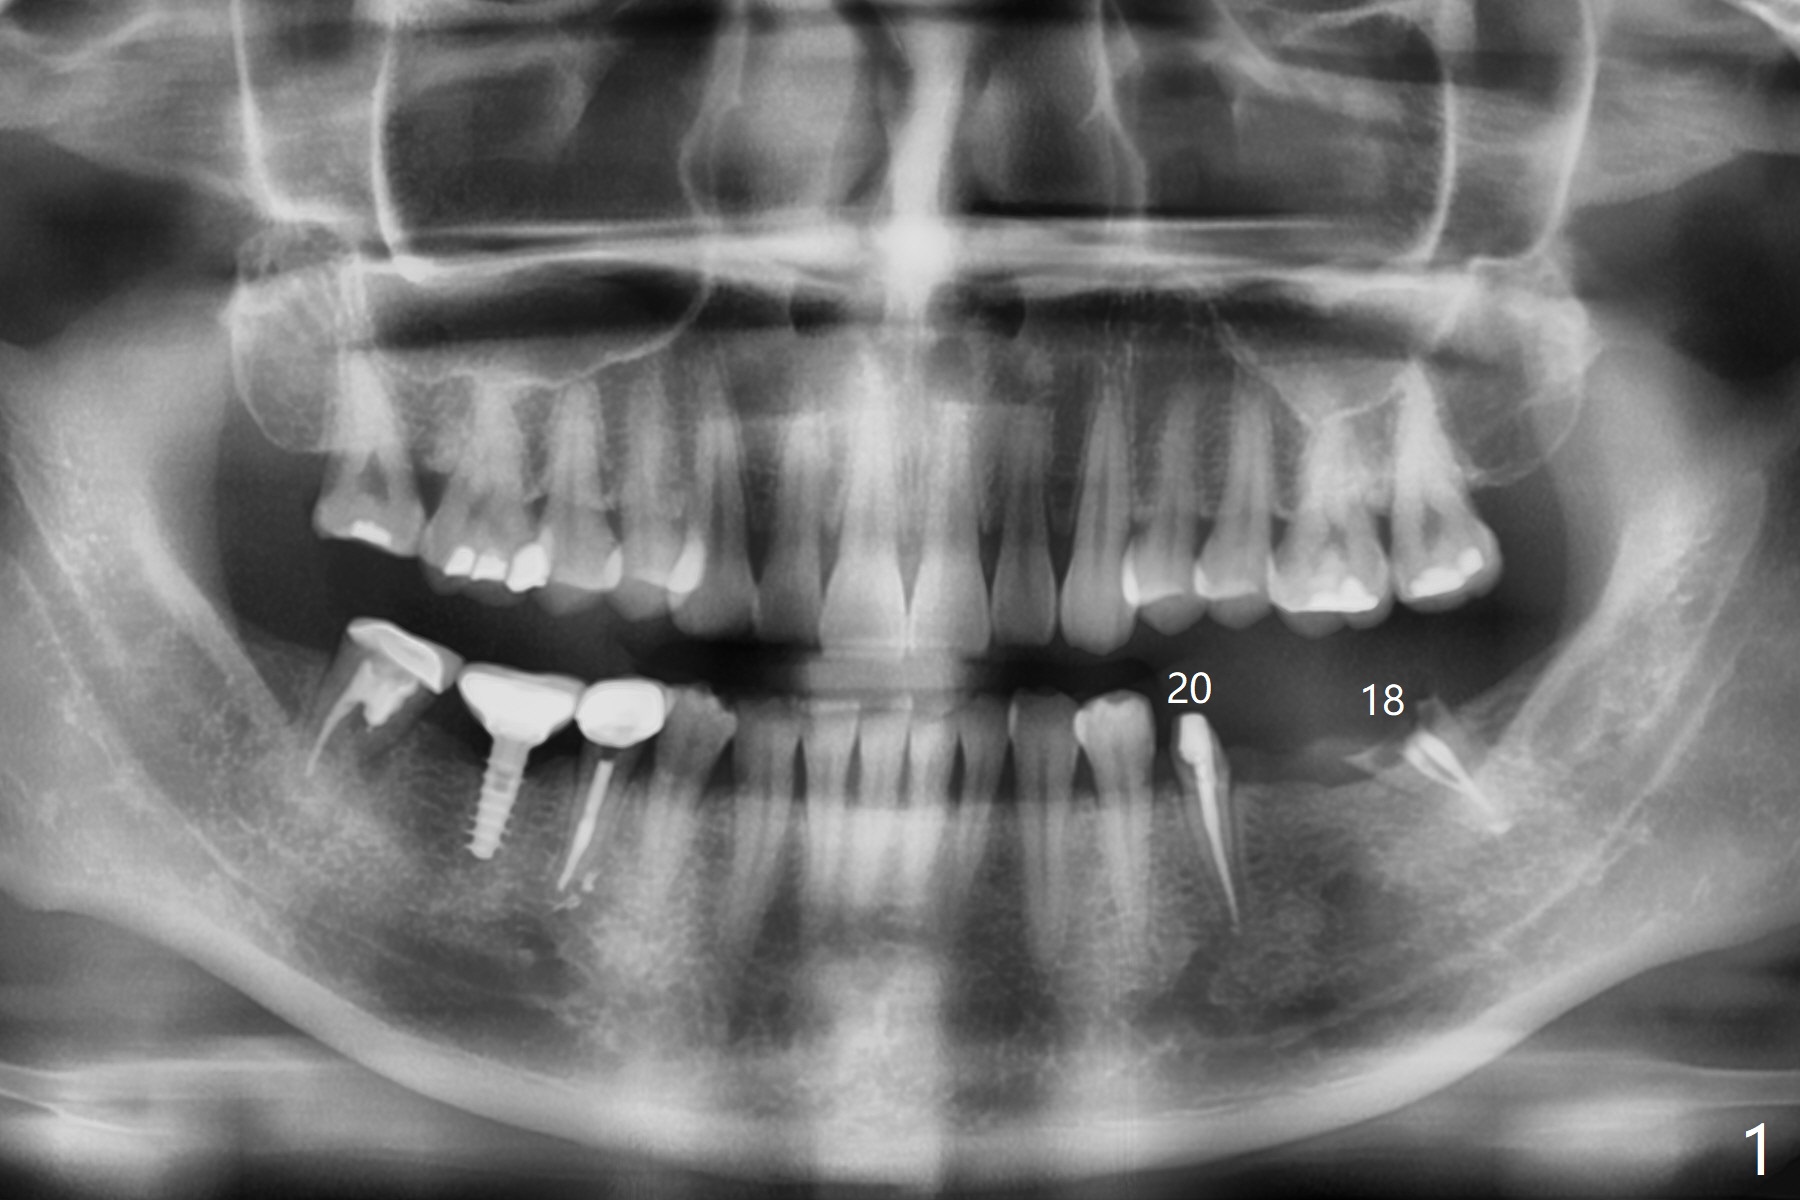

Smaller Implants for Thicker Surrounding Bone

A 46-year-old woman has a failed FPD 18-20 (Fig.1). To have thicker buccal bone, the 5 mm implants at #18 (Fig.2) and 19 (Fig.3) seem to be a little large. Smaller (4.5 mm) will be more appropriate so that the coronal threads of the implant at #18 will be more securely covered by the regenerating bone. In the same manner, the implant to be placed in the healed site of #19 will have more buccal bone when the diameter of the implant reduces.